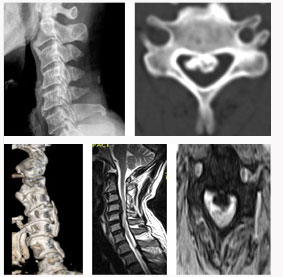

척추관 협착증의 방사선 소견